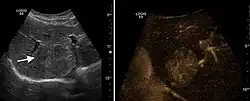

HCC appearance on 2D ultrasound is that of a solid tumor, with imprecise delineation, with heterogeneous structure, uni- or multilocular (encephaloid form). An "infiltrative" type is also described which is difficult to discriminate from liver nodular reconstruction in cirrhosis. Typically HCC invades liver vessels, primarily the portal veins but also the hepatic veins . Doppler examination detects a high speed arterial flow and low impedance index (correlated with described changes in tumor angiogenesis). The spatial distribution of the vessels is irregular, disordered. CEUS examination shows hyperenhancement of the lesion during the arterial phase. During the portal venous phase there is a specific "wash out" of ultrasound contrast agent (UCA) and the tumor appears hypoechoic during the late phase. Poorly differentiated tumors may have a stronger wash out leading to an isoechoic appearance to the liver parenchyma during portal venous phase. This appearance was found in approx. 30% of cases. The described changes have diagnostic value in liver nodules larger than 2 cm.

It is the most common liver malignancy. It develops secondary to cirrhosis therefore, ultrasound examination every 6 months combined with alpha fetoprotein (AFP) determination is an effective method for early detection and treatment monitoring for this type of tumor . Clinically, HCC overlaps with advanced liver cirrhosis (long evolution, repeated vascular and parenchymal decompensation, sometimes bleeding due to variceal leakage) in addition to accelerated weight loss in the recent past and lack of appetite.

Hepatocellular carcinoma (HCC)